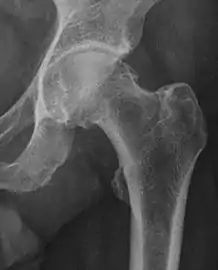

Radiograph of a pincer type impingement.

Projectional radiography ("X-ray")is often considered first line for FAI.[10] Anterior-posterior pelvis and a lateral image of the hip in question should be attained.[10] A 45-degree Dunn view is also recommended.[10][19]